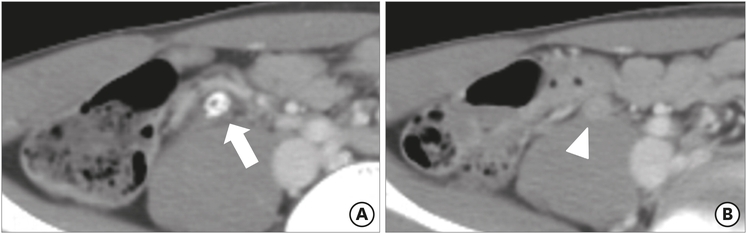

The mean maximal diameter of the appendix was 9.56 mm in the true appendicitis group and 7.28 mm in the negative appendicitis group. According to the definition of appendiceal enlargement (>8 mm in maximal diameter), 3 patients (23.1%) in the negative appendicitis group had an enlarged appendix, while 60 patients (68.2%) in the true appendicitis group had appendiceal enlargement (Fig. 1). This difference was statistically significant (p=0.002). Periappendiceal fat inflammation, or fat stranding, was noted in 2 patients (15.4%) in the negative appendicitis group and 43 patients (48.9%) in the true appendicitis group (p=0.023) (Fig. 2). For the other measured findings, there were no significant differences between the groups. The ACT findings are summarized in Table 2, along with their odds ratios and 95% confidence intervals (CIs).

Fig. 2

Preoperative ACT findings for a 13-year-old male patient, who was demonstrated to have lymphoid hyperplasia: (A) appendicolith (arrow) and (B) luminal distension (arrowheads) were observed, but there were no other diagnostic abnormalities in ACT.

ACT, abdominal computed tomography.